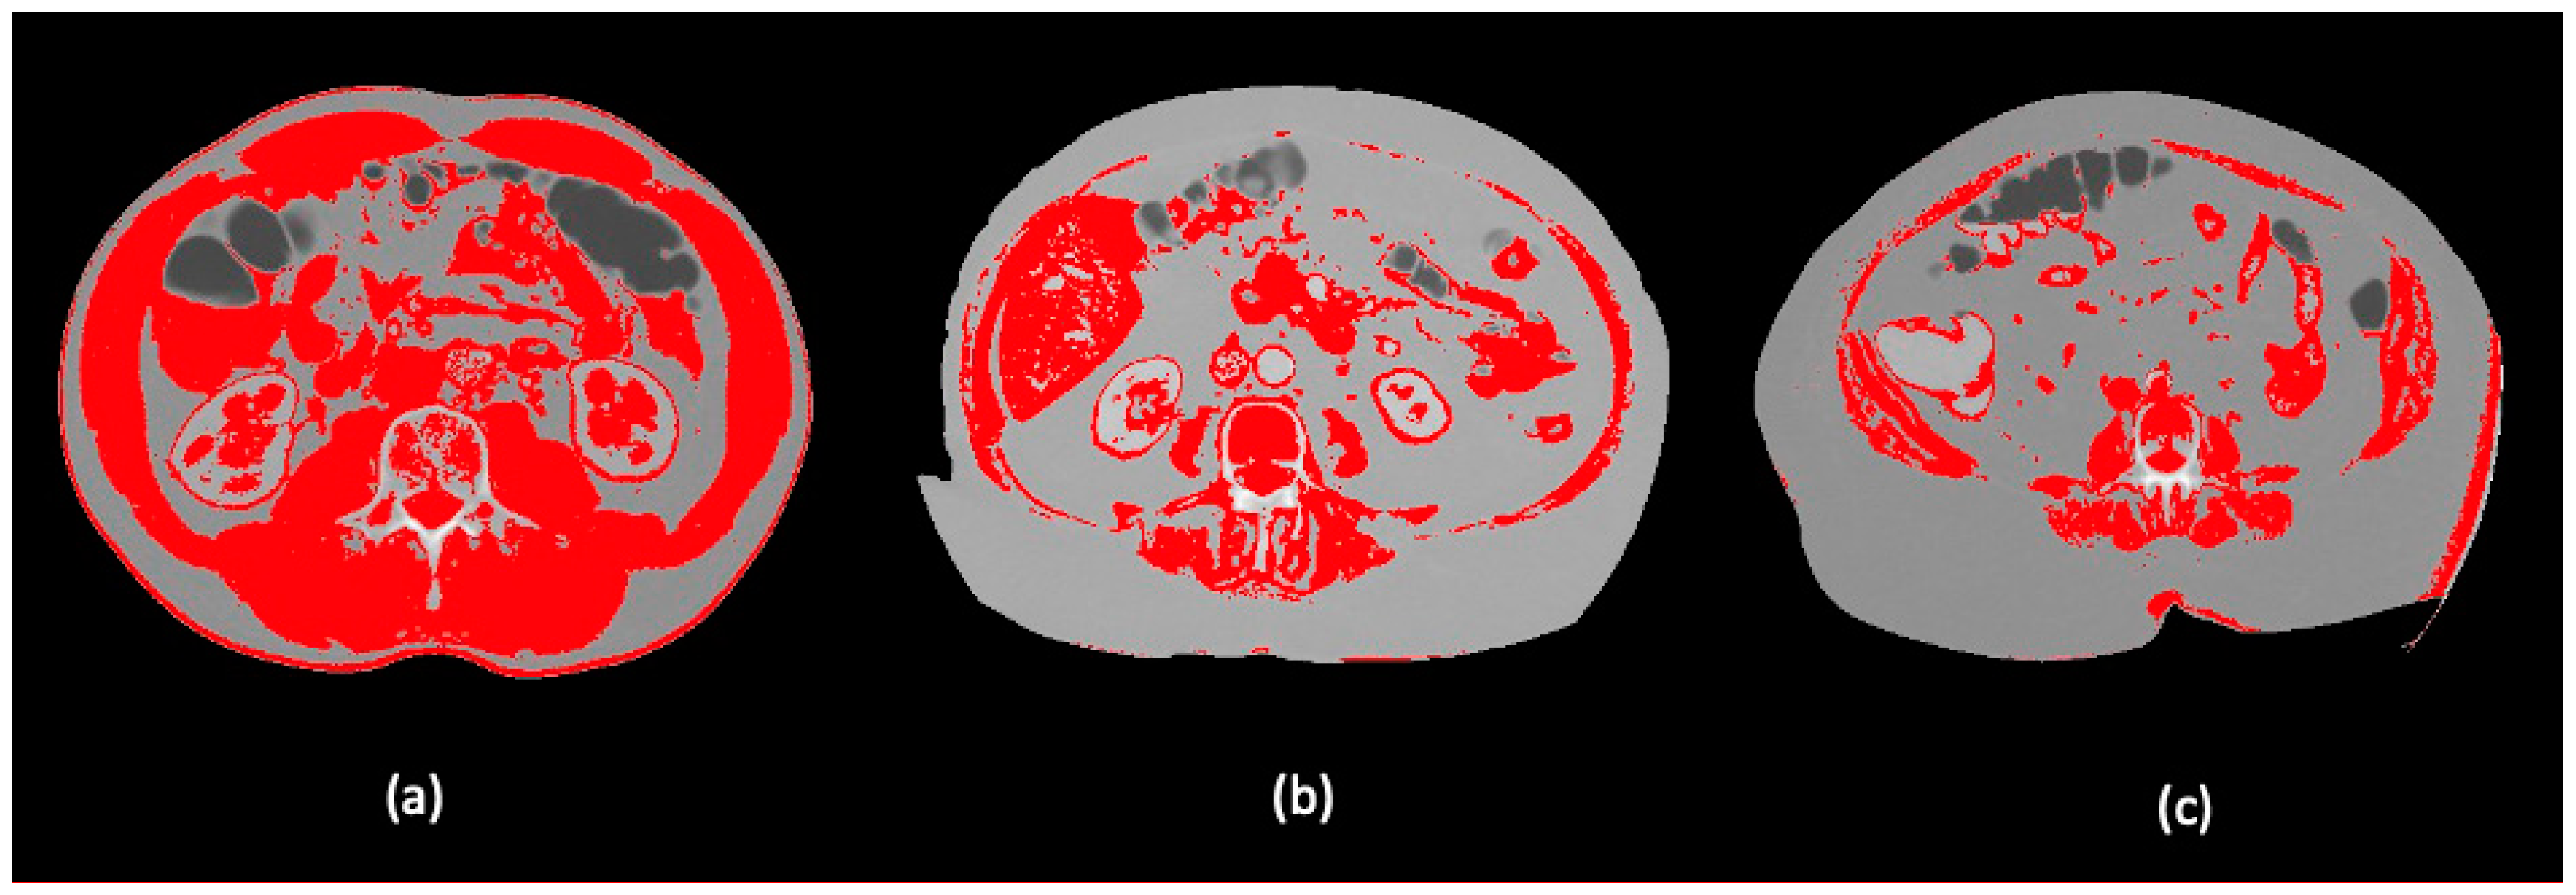

2.4. Body Composition Protocol

- Gomez-Perez, S.; McKeever, L.; Sheean, P. Tutorial: A Step-by-Step Guide (Version 2.0) for Measuring Abdominal Circumference and Skeletal Muscle from a Single Cross-Sectional Computed-Tomography Image Using the National Institutes of Health ImageJ. J. Parenter. Enter. Nutr. 2020, 44, 419–424. [Google Scholar] [CrossRef] [PubMed]